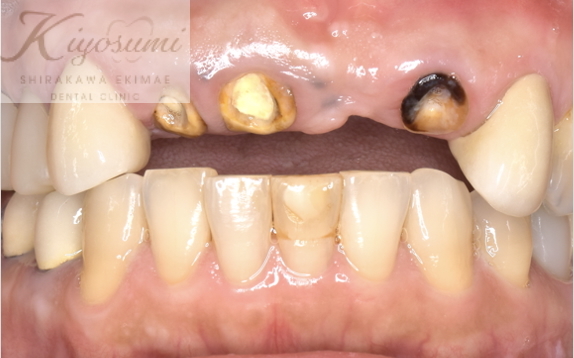

| 主訴 | 歯が揺れて噛めないので、噛めるようにして欲しい。 |

| 治療内容 | 基本的な歯周病治療、根の治療を実施し、歯の高さが足りない箇所は歯冠長延長術、保存が難しい歯は一部歯根分割抜去を行いました。欠損部はインプラントを用いず、ジルコニアブリッジで仕上げています。 |

| 想定されたリスク | ※残存している歯の本数が少ないため、残っている歯だけでブリッジを行うには長期予後が見込めない可能性があり、患者さんにご理解をいただいたうえで被せ物を行っています。 ※歯周病治療や根の治療をしても歯を残せない可能性がありました。 |